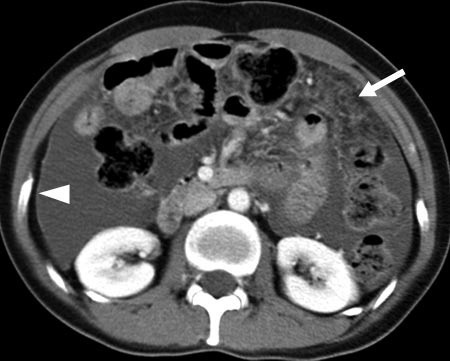

결핵은 결핵균에 감염되어 발생하는 만성감염 질환입니다. 결핵균은 주로 폐를 침범하지만, 뼈, 뇌, 신장, 심장 등 다른 장기에도 침범할 수 있습니다. 결핵성 복막염은 결핵균에 감염되어 복막에 염증이 생기는 질환입니다. 복막은 복강 내 기관을 싸고 있는 막으로, 결핵균에 감염되면 복막에 염증이 생기고, 복수가 차는 증상이 나타납니다. 1. 원인 결핵성 복막염은 결핵균은 감염된 후, 혈액을 통해 복막으로 전파되어 발생합니다. 결핵균은 폐를 침범한 후, 혈액을 통해 전신으로 퍼져나갈 수 있습니다. 결핵성 복막염은 면역력이 약한 사람에게서 더 많이 발생합니다. 따라서, 에이즈, 암, 당뇨병, 장기 이식 수술을 받은 사람 등은 결핵성 복막염에 걸릴 위험이 높습니다. 2. 증상 결핵성 복막염의 증상은 다음과 같습니..